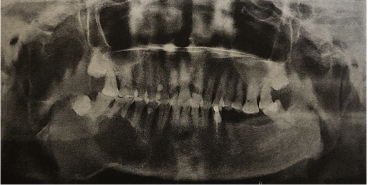

以下图为例:

上图是右下颌骨的成釉细胞瘤,全景片显示右下颌骨体部及升支多囊性、透射性改变,边界清楚;下颌角区颌骨膨隆,46及47牙根截断状吸收。